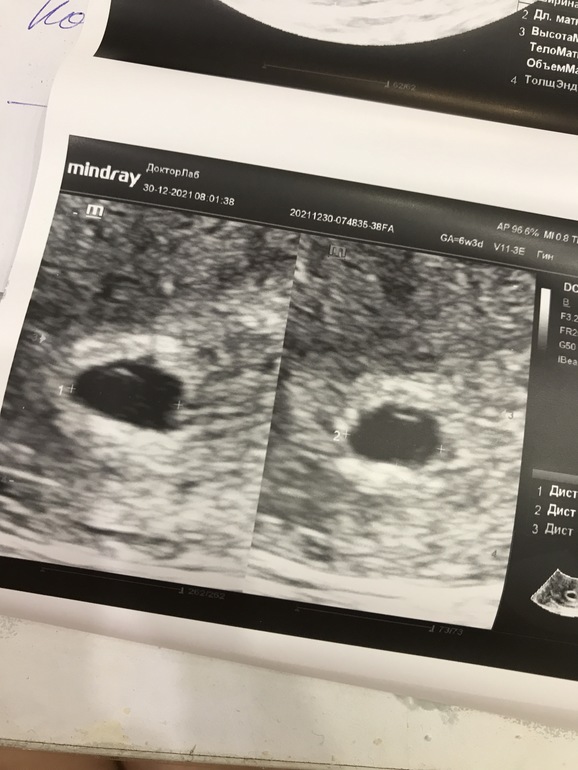

УЗИ, КТГ, доплерДевочки , помогите разобраться .. последние месячные были 15 ноября , то есть срок сегодня должен быть 6,3 , сегодня утром была на узи , думала услышать сердечко и увидеть эмбрион , но узист не увидел , сказал что срок на 5 недель! Увидел плодное яйцо и желточный мешочек и сказал придти через 2 недели , но говорит ничего плохого не вижу .. я так переживаю почему такое расхождение сроков , и появится ли эмбрион через 2 недели , или это уже все ((

На снимке сказал что это такой желточный мешочек